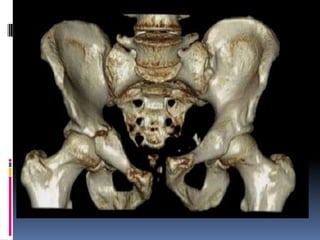

Grupo C-2

disrupción completa en hueso iliaco: C-21, articulación sacroiliaca: C-2-2 ó hueso sacro C-2-3.

Fractura tipo C2 : Fractura bilateral del sacro (completa del ala sacra izquierda e

incompleta de la derecha) por cizallamiento vertical en una mujer de 29 años.

Grupo C-2 Fracturas concompromiso unilateral completo y contralateral incompleto del anillo posterior. Se diferencian según la ubicación del rasgo con disrupción completa en hueso iliaco: C-21, articulación sacroiliaca: C-2-2 ó hueso sacro C-2-3.

 Fractura tipo C2: Fractura bilateral del sacro (completa del ala sacra izquierda e incompleta de la derecha) por cizallamiento vertical en una mujer de 29 años.